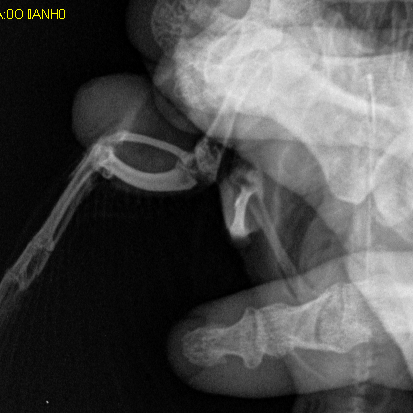

@Zosia @ZosiaБольше нигде никаких образований не нашли. Сегодня съездили к орнитологу. Опухоль плотная, не двигается. Сделали рентген (фото ниже). Сказали нужна операция, и скорее всего крыло придется ампутировать. Лечение никакое не назначили.

Выложенный снимок фрагментарен, но зона нарушения вокруг сустава видна